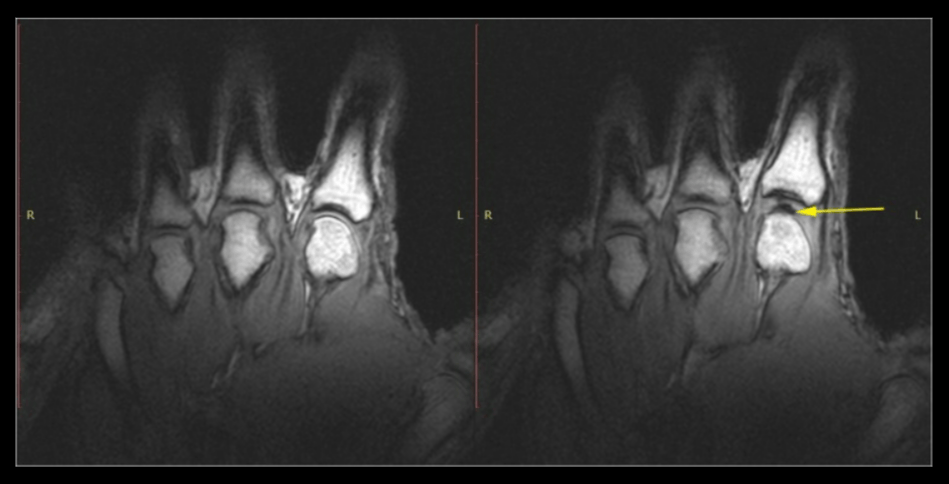

Слева: рука в покое перед растрескиванием. Справа: та же рука после хруста от растяжения. Обратите внимание на тёмную межсуставную полость (жёлтая стрелка). Источник изображения: pubmed.ncbi.nlm.nih.gov

Когда вы резко растягиваете суставы, давление внутри жидкости падает, и возникают газовые полости/пузырьки, которые мгновенно частично схлопываются. Именно этот процесс и даёт характерный звук. Хотя точный момент (образование или частичное схлопывание) ещё обсуждается.